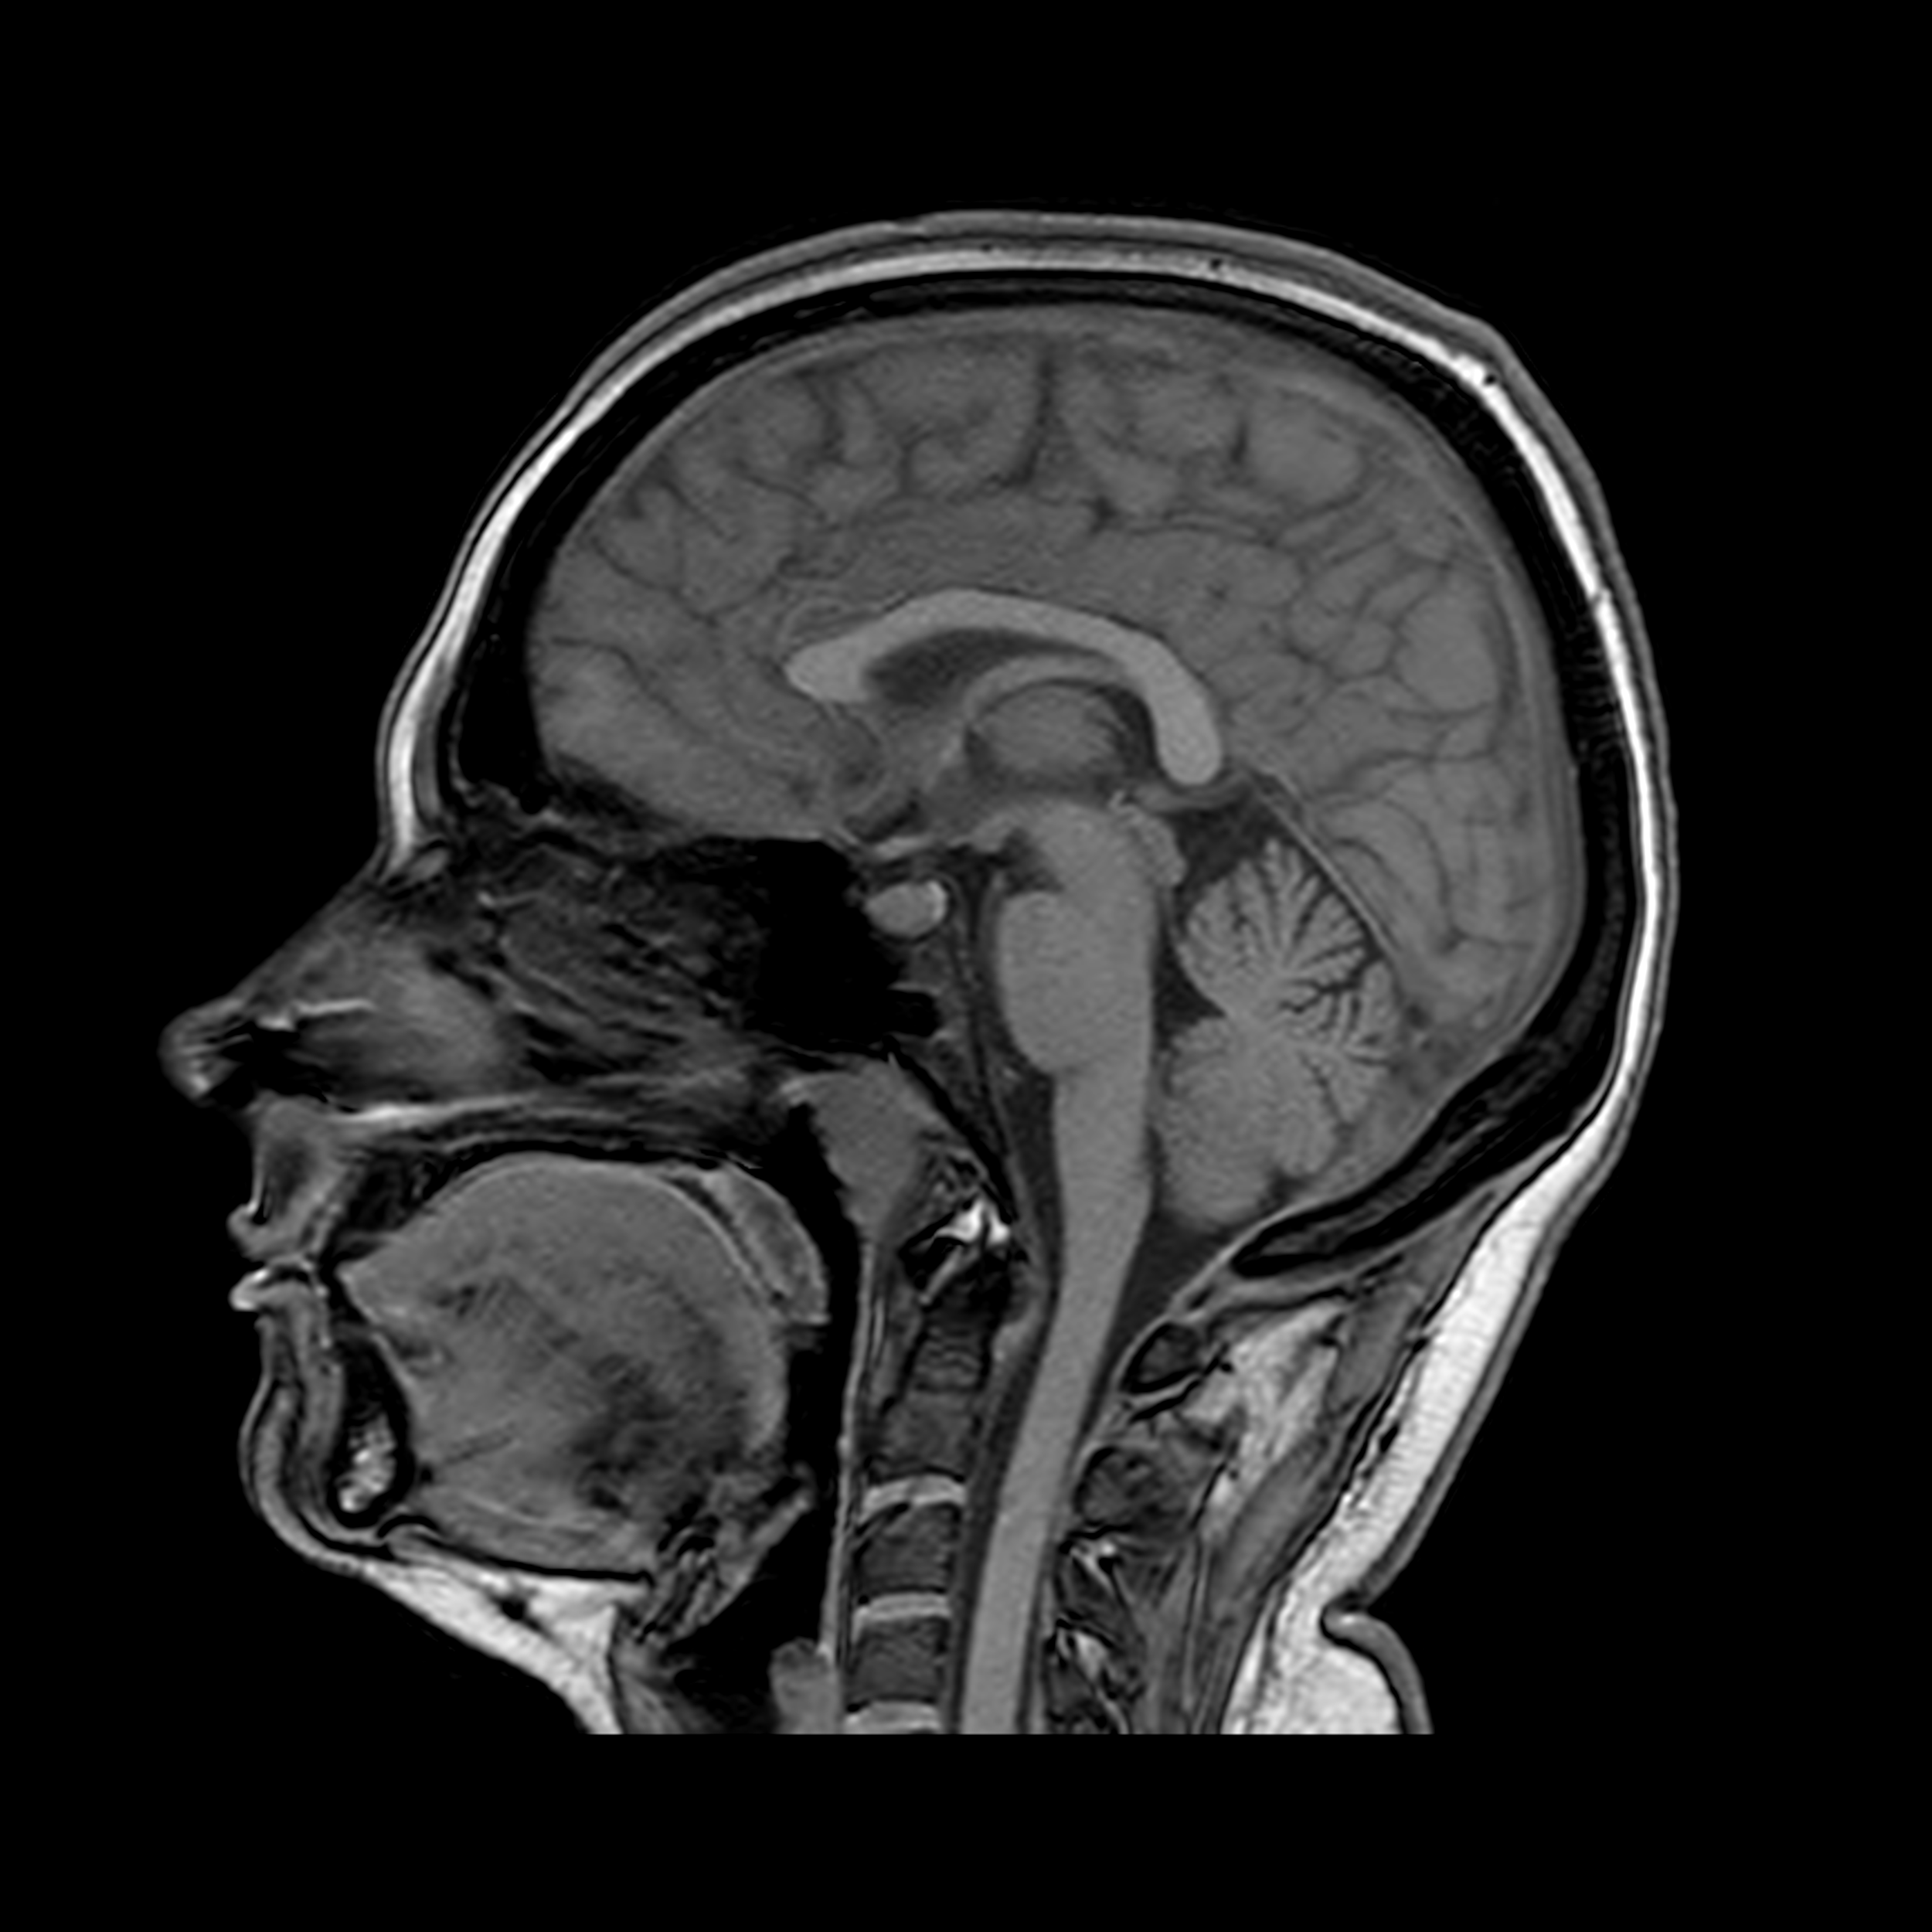

Сагиттальная плоскость